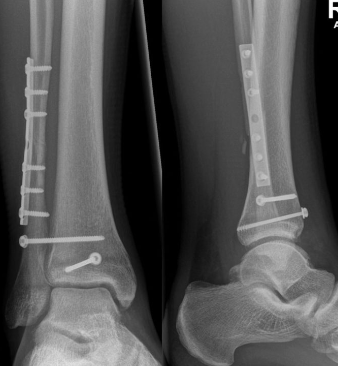

3. 골절

발목 골절은 발목 뼈 중 하나 이상이 부러진 경우를 말합니다. 이는 추락, 사고 또는 스포츠 부상과 같은 다양한 이유로 발생할 수 있습니다.

치료 방법 :

- 캐스트, 스플린트 또는 브레이스로 고정합니다.

- 일부 경우에는 부러진 뼈를 다시 정렬하고 안정화하기 위해 수술이 필요할 수 있습니다.

- 힘과 기동성을 되찾기 위한 물리 치료가 필요할 수 있습니다.